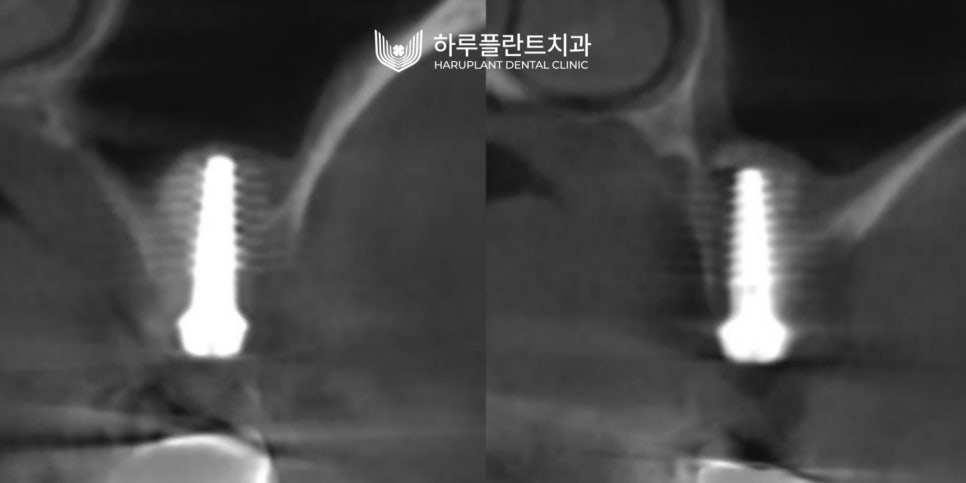

▲ 무절개 상악동 거상술과 동시에 임플란트 식립 (우측) / 무절개 상악동 거상술과 동시에 임플란트 식립 (좌측)

2023.05 ▲ 3개월 후 최종보철완성(우측) / 3개월 후 최종보철완성(좌측)